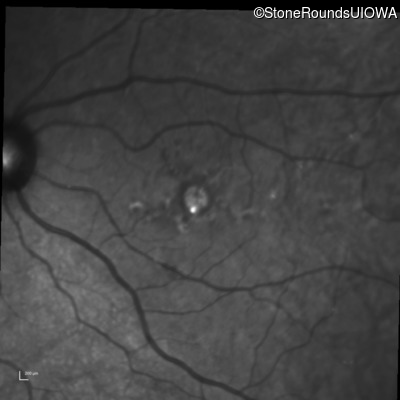

Infrared Fundus Photograph - Right - 20/20 +2

Exemplar